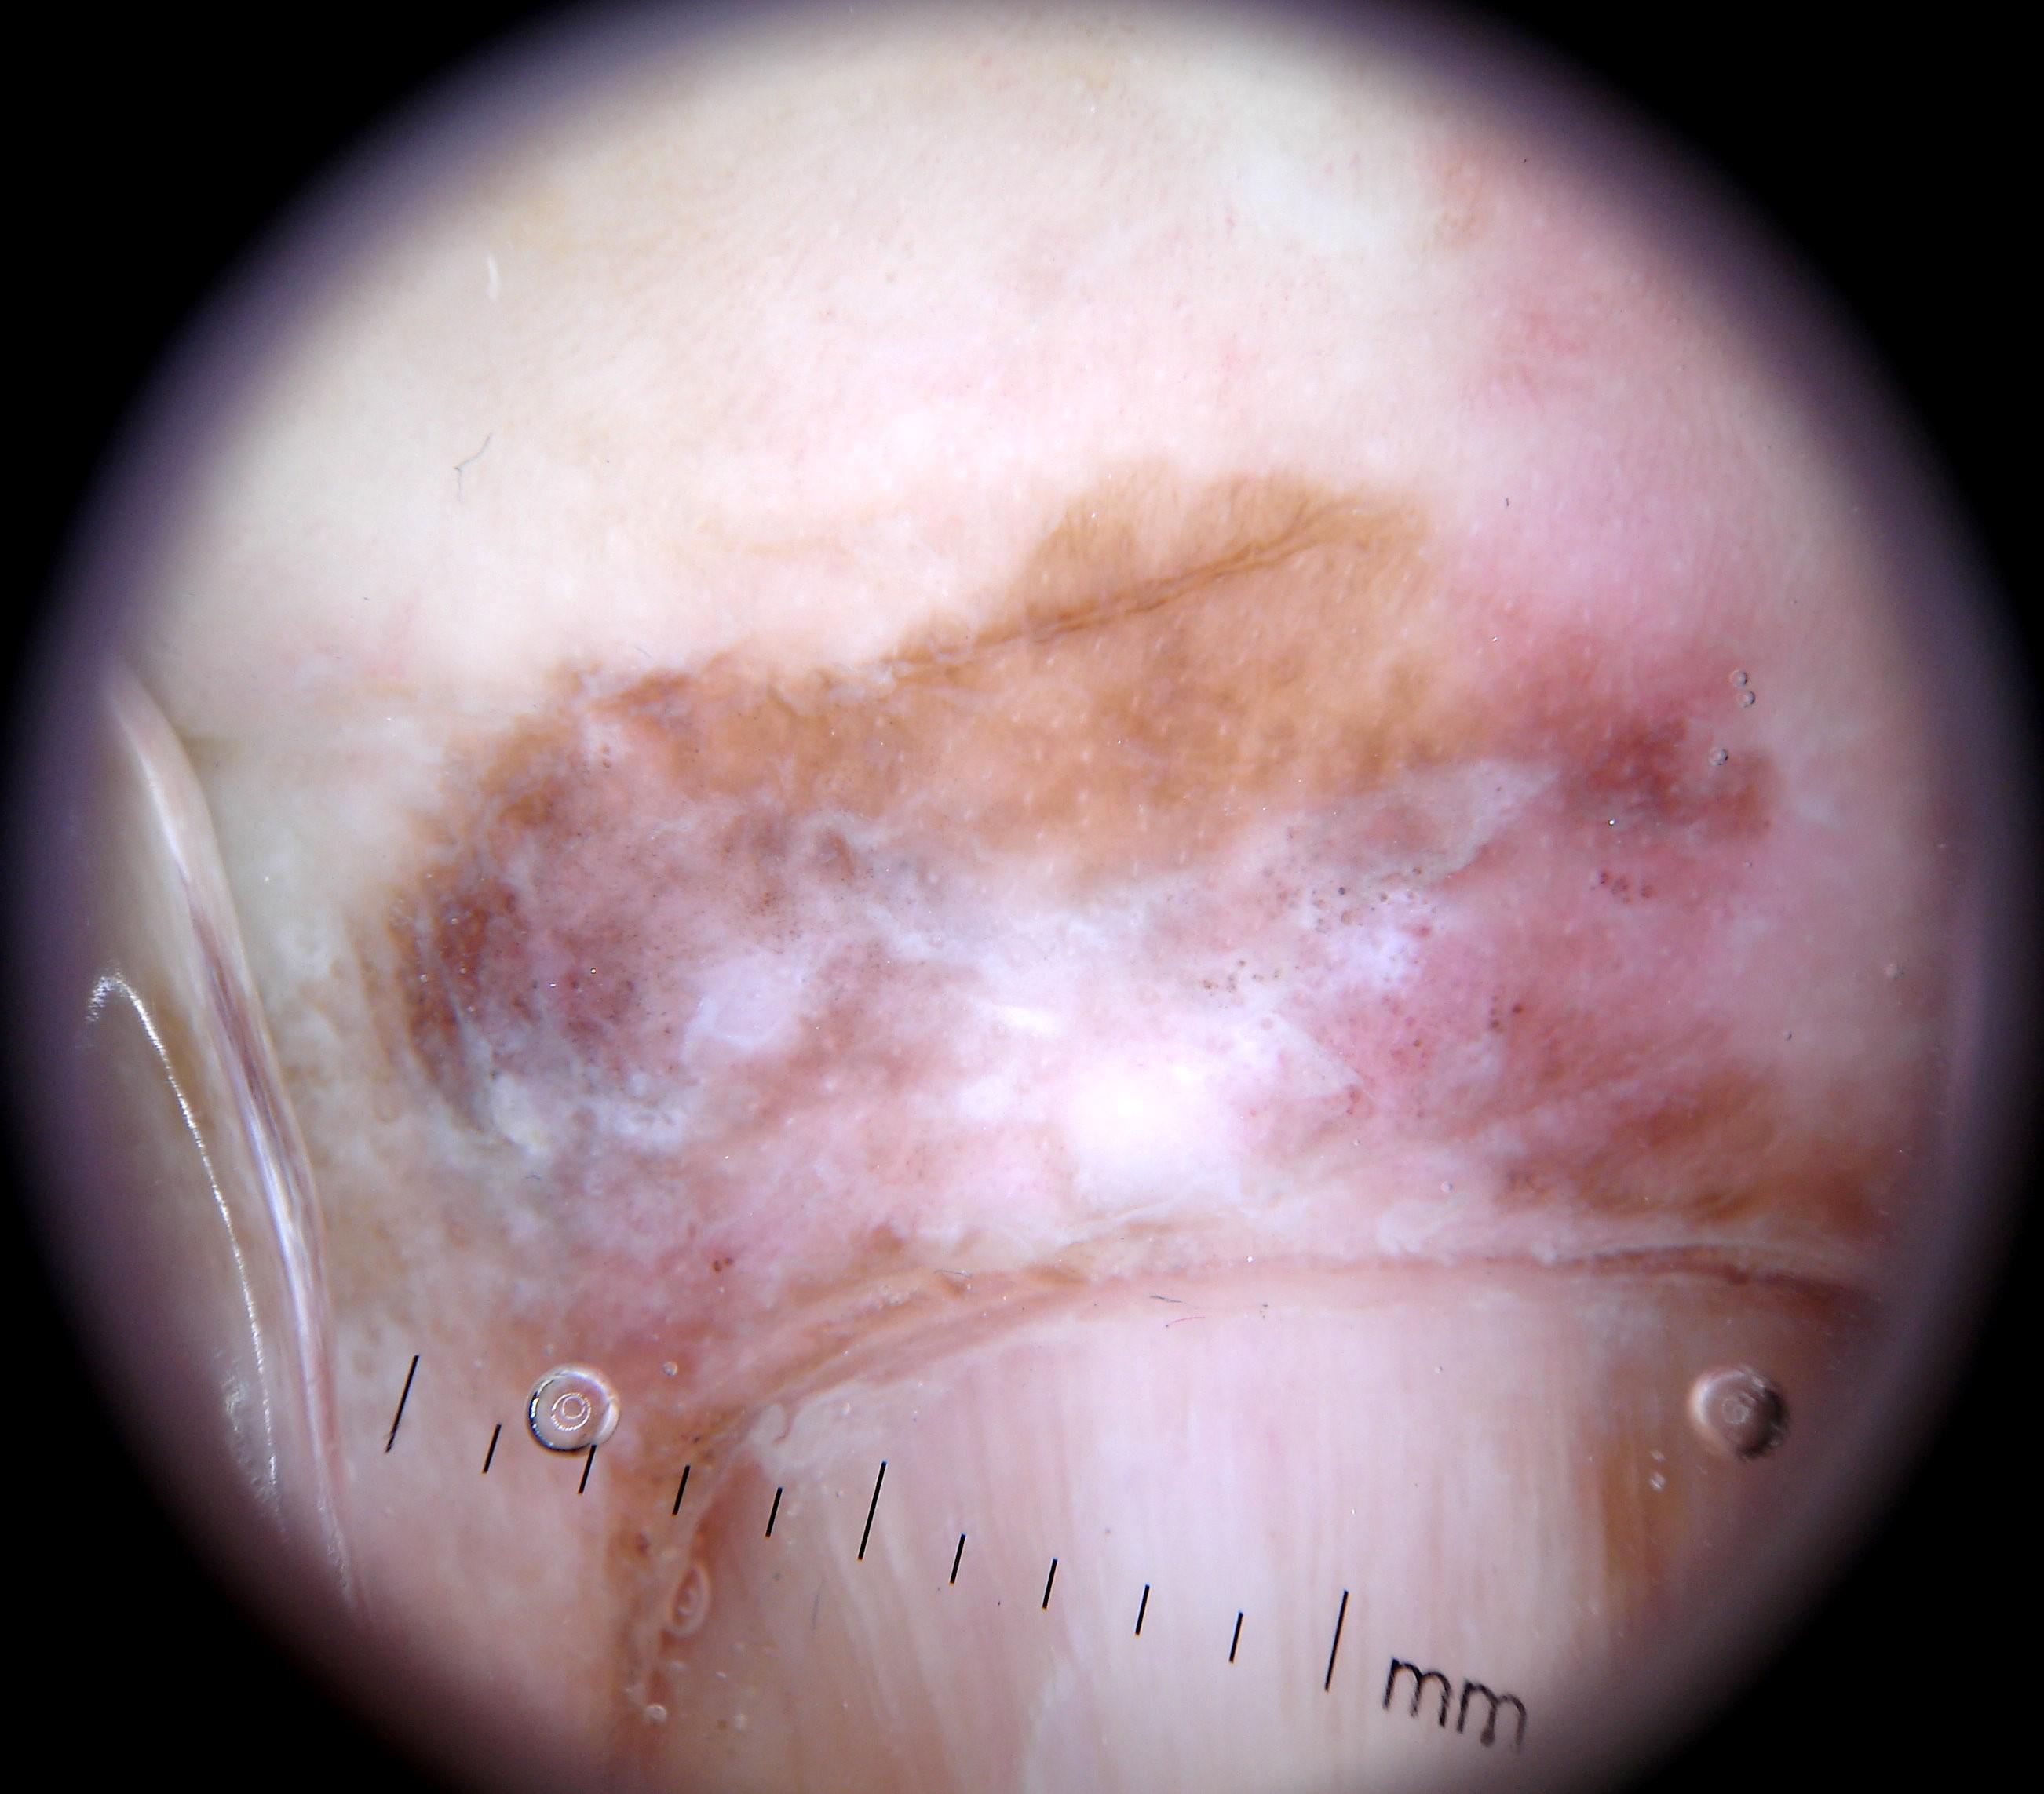

{

"age_approx": 65,

"anatom_site_general": "upper extremity",

"anatom_site_special": "acral NOS",

"concomitant_biopsy": true,

"dermoscopic_type": "contact polarized",

"diagnosis_1": "Malignant",

"diagnosis_2": "Malignant melanocytic proliferations (Melanoma)",

"diagnosis_3": "Melanoma in situ",

"diagnosis_confirm_type": "histopathology",

"family_hx_mm": false,

"image_type": "dermoscopic",

"mel_thick_mm": "0.00",

"melanocytic": true,

"patient_id": "IP_3069248",

"personal_hx_mm": false,

"sex": "male"

}